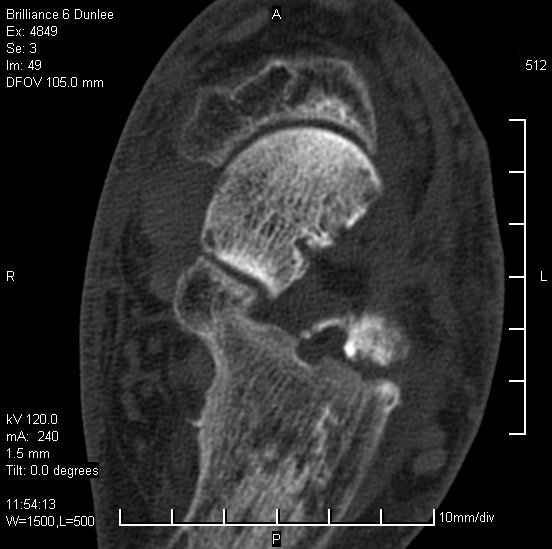

На лечении находится пациент 35 лет. Травма в сентябре 2008 г.- открытый вывих таранной кости

В день травмы ПХО, вправление вывиха, трансартикулярная фиксация. Рана зажила первично. С января нагрузка на конечность. С конца апреля- болевой синдром. На рентгенограммах и КТ признаки ас. некроза таранной кости, артроз подтаранного и голеностопного суставов.

У больного тотальный ас. некрох блока таранной кости, заинтересованы голеностопный и подтараный суставы. Эндопротезирование маловероятно на некротизированную кость. Изолированный подтаранный артродез таран не спасет.При артродезе всю некротизированную кость придется убрать.А далее замещение либо за счет большеберцовой кости, или удлинение на регенерате.